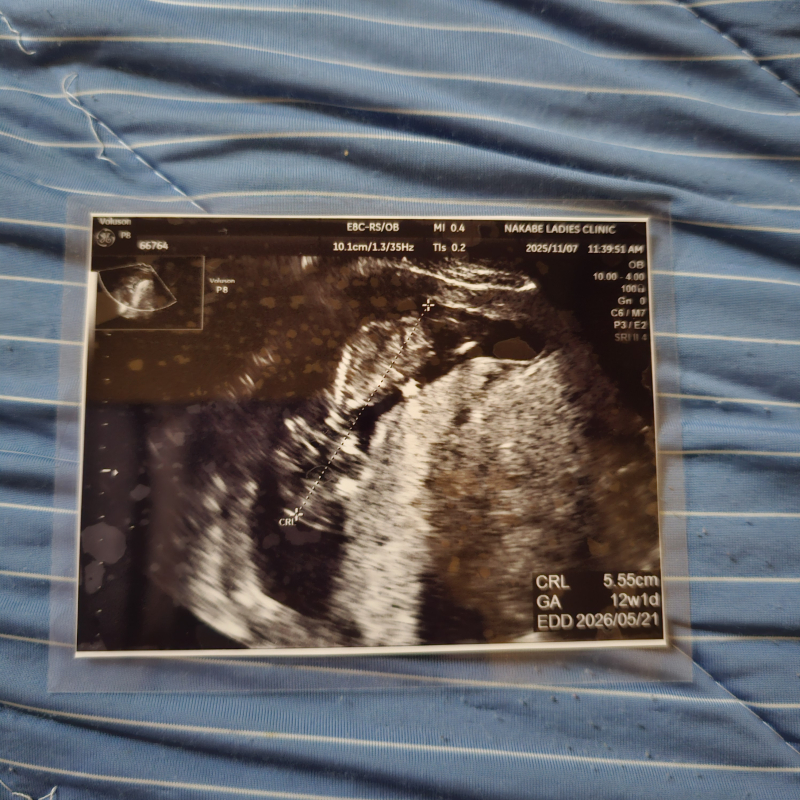

ちなみに11月7日にあった健診でエコーを見たら、赤ちゃんのサイズは5.55cmでした。